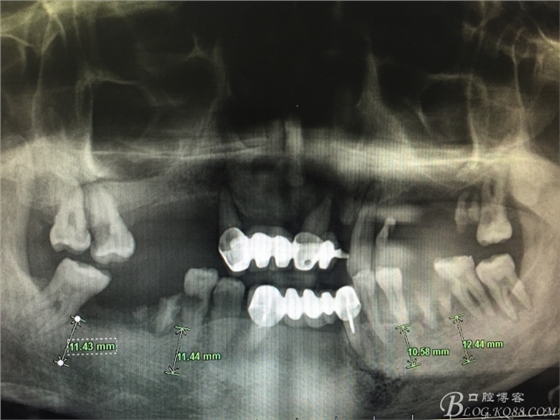

患者37歲 男 全口牙周病 手術(shù)一次完成 全程3小時(shí)全口種植修復(fù)全口種植修復(fù)全口種植修復(fù)全口種植修復(fù)全口種植修復(fù)全口種植修復(fù)全口種植修復(fù)全口種植修復(fù)全口種植修復(fù)全口種植修復(fù)全口種植修復(fù)全口種植修復(fù)全口種植修復(fù)全口種植修復(fù)全口種植修復(fù)